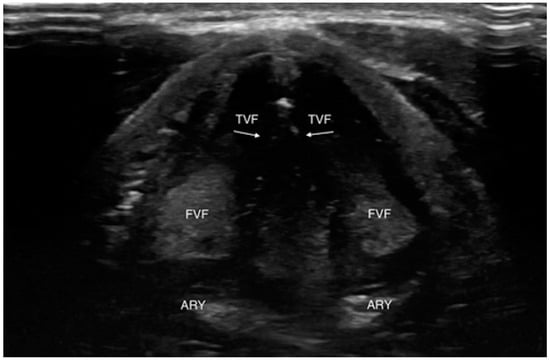

4.1.3. Laryngeal Edema Assessment Pre-Extubation

4.2. B: US and Breathing